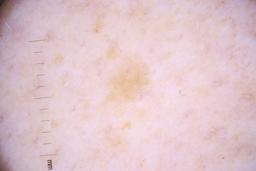

ISIC_4077341

- Challenge 2020: Training

- IP_1969685 IL_9238622

Clinical

| diagnosis_1 | Benign |

| diagnosis_confirm_type | serial imaging showing no change |

| image_type | dermoscopic |

Showing first 50 images.